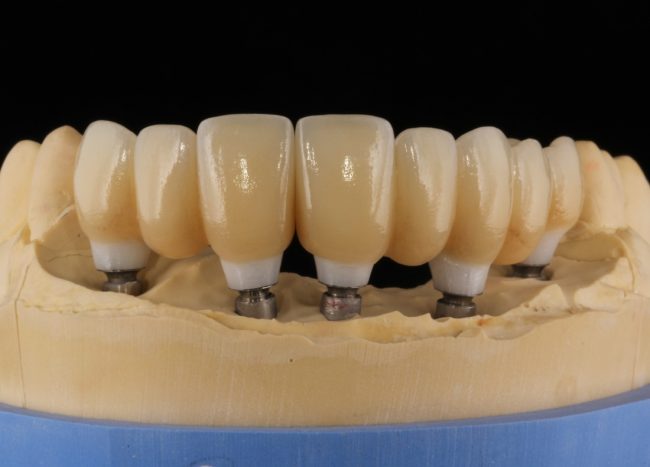

Кстати, вот часть проведенного лечения у пациента с фотографии выше:

И это всего лишь временные коронки!)

Конечно, из этих общих правил существуют исключения. Так, для протезирования по схеме All-On-4 или All-On-6 мы вполне можем использовать имплантаты одного диаметра:

а проблема распределения нагрузки решается за счет объединения их в единую протетическую конструкцию.